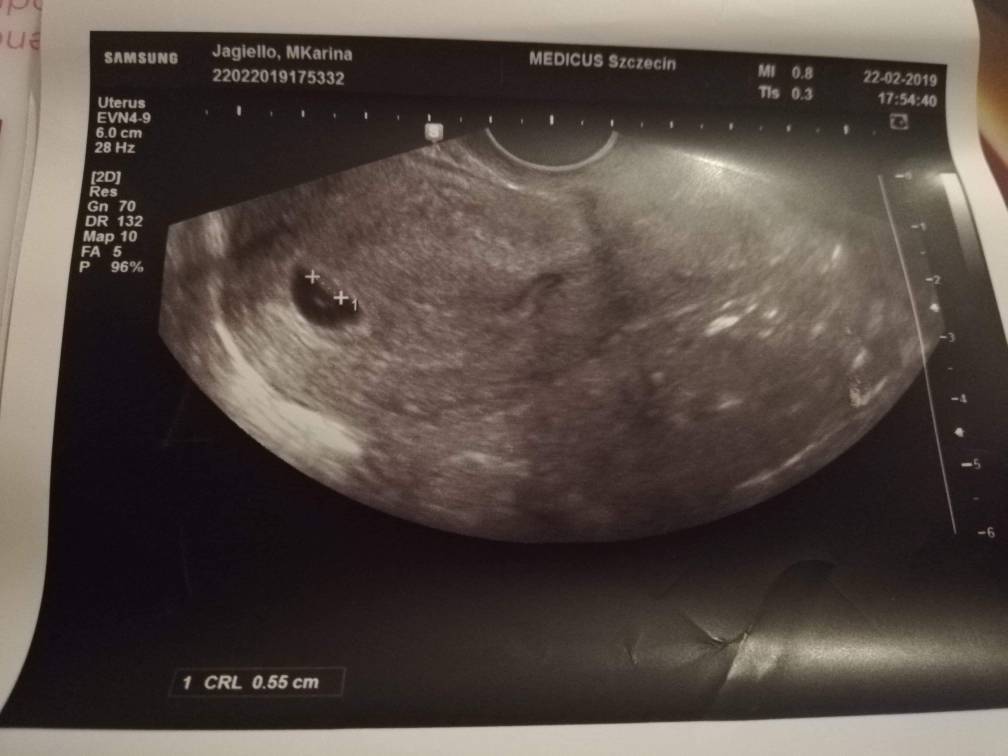

SuperTo za okolo 9 dni juz bedzie zarodek. U mnie 5+6 wygladalo tak jak na pierwszym foto.

A 6+5 jak na drugim i tu juz byla akcja serduszka.Zobacz załącznik 973845Zobacz załącznik 973847